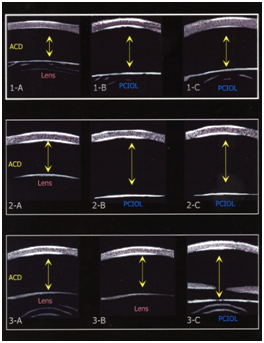

Three patients (2 females and 1 male), ranging in age from 7 months to 43 months with a mean age of 23.3 months (SD+18.2) were studied. Figure 1 displays the UBM images for each of the 3 cases with arrows depicting measured ACD for each eye both preoperatively and postoperatively. Preoperative axial length measurements and UBM measurements of ACD are listed in Table 1. Case 1 had a change in ACD OD of 0.94 (p=0.0019) from preoperative to postoperative measurements after cataract surgery with posterior caspsulorhexis with optic capture. The left eye underwent cataract surgery with placement of a posterior chamber IOL in the capsular bag without optic capture. The postoperative ACD difference between OD and OS was 1.05 mm (p=0.0010). Case 2 had a change in ACD OD of 1.48 mm (p=0.0003) from preoperative to postoperative measurements. The postoperative ACD difference, after bilateral cataract surgery with posterior capsulorhexis with optic capture, between OD and OS was not statistically significant: 0.23 mm (p=0.1058). Case 3 underwent cataract surgery with posterior chamber IOL implantation with optic capture OS. There was an ACD change OS of 0.29 mm (p=0.0157) from baseline preoperative to postoperative measurements.

Figure 1 1 (A-C) UBM images for case 1

i. 1A: Preoperative ACD image OD

ii. 1B: Postoperative ACD image with IOL placement in-the-bag OS

iii. 1C: Postoperative ACD image after IOL optic capture OD

2 (A-C) UBM images for case 2

i. 2A: Preoperative ACD image OD

ii. 2B: Postoperative ACD image after IOL optic capture OD

iii. 2C: Postoperative ACD image after IOL optic capture OS

3 (A-C) UBM images for case 3

i. 3A: Preoperative ACD image OD

ii. 3B: Preoperative ACD image OS

iii. 3C: Postoperative ACD image after IOL optic capture OS